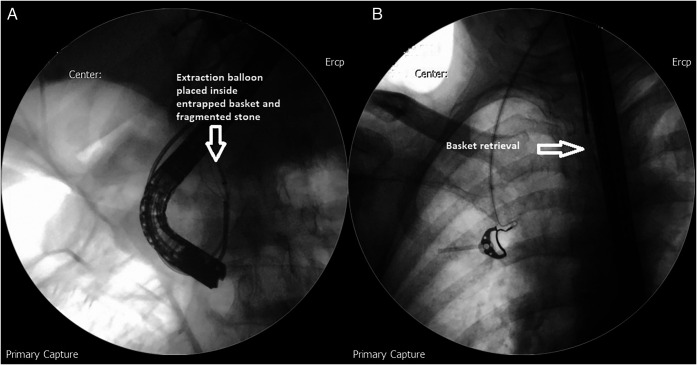

The stone was grasped with the Dormia basket, and multiple attempts to crush and retrieve it remained unsuccessful, resulting in the entrapment of the Dormia basket with the impacted stone (Figure 2). Balloon sphincteroplasty to 16 mm was performed for extraction of the entrapped basket and stone with no success (Figure 3). Subsequently, it was decided to use a novel technique of cholangioscope-guided EHL to dislodge and retrieve the entrapped basket. Basket wires were cut from the proximal end to release tension for the facilitation of retrieval. A single-operator intraductal cholangioscope was advanced with direct visualization of the stone and entrapped basket. EHL was performed for stone fragmentation (Figure 4). After fragmentation, a wire-guided extraction balloon was placed within the entrapped basket and fragmented stones. The extraction balloon was then inflated to 15 mm, which released the entrapped wires, and subsequently, the basket was retrieved successfully (Figure 5). Stone fragments were retrieved with the extraction balloon, and an occlusion cholangiogram confirmed clear ducts (Figure 6). The patient was discharged on the same day with no procedure-related complications.